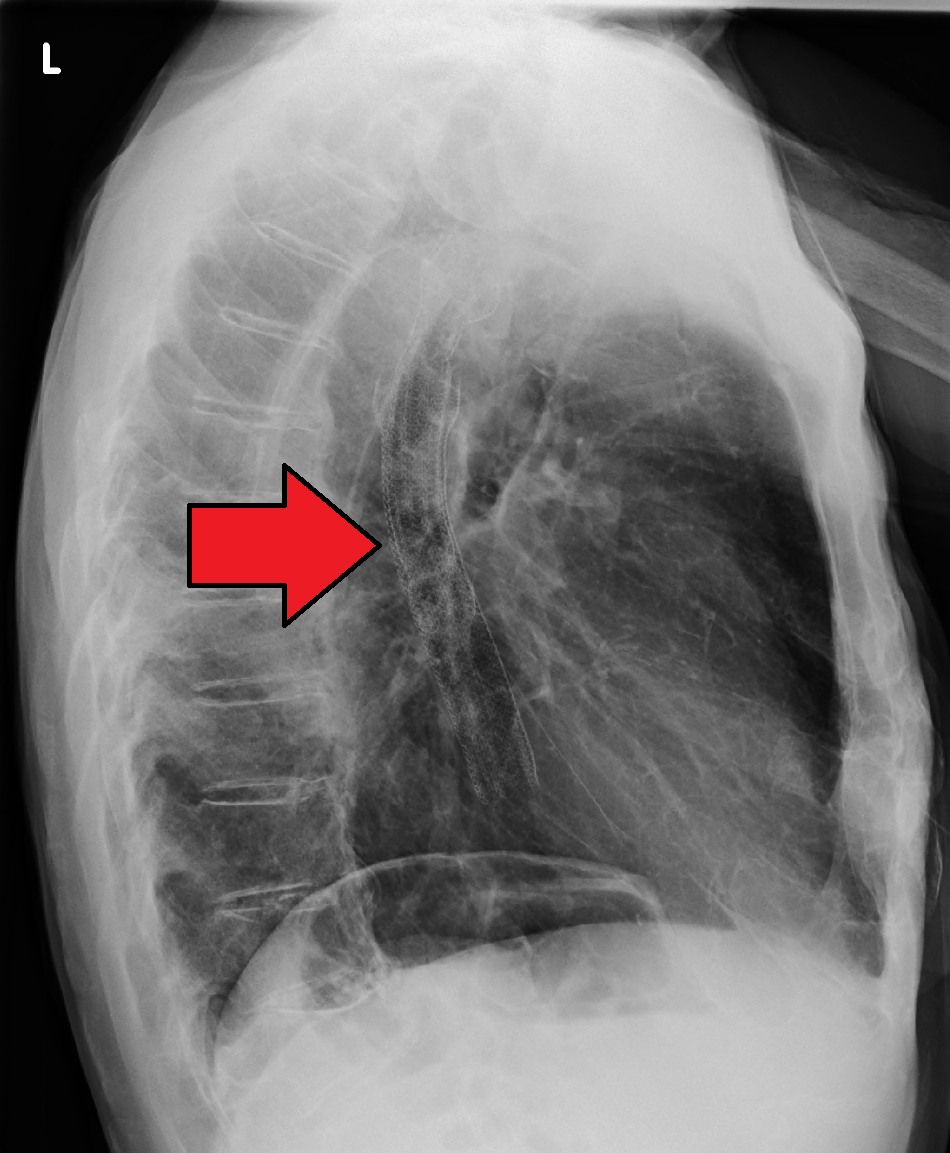

종양이 있으면 삼킬 때 식도의 정상적인 수축을 방해하여[112] 메스꺼움, 구토, 음식물 역류, 기침을 유발할 수 있다.[112] 식도와 기관 사이에 누공이 생기면 음식물이 기도로 들어가 흡인성 폐렴의 위험이 높아진다.[110] 음식을 먹거나 마실 때 기침을 한다면 흡인성 폐렴의 초기 증상일 수 있다.[116] 종양 표면에서 출혈이 발생하면 피를 토할 수 있다. 진행성 질환에서는 주변 조직 압박으로 상기도 폐쇄, 상대정맥 증후군이 발생할 수 있고, 고칼슘혈증이 나타날 수도 있다.[112]

암이 다른 곳으로 퍼지면 전이된 부위에 따라 증상이 나타난다. 흔한 전이 부위는 인근 림프절, 간, 폐, 뼈 등이다.[112] 간 전이는 황달, 복부 팽만(복수)을 유발할 수 있다. 폐 전이는 폐 주위 체액 증가(흉막 삼출)로 인한 호흡 장애, 호흡 곤란 등의 증상을 유발할 수 있다.

바륨 삼킴 검사나 바륨 식사 검사에서 폐쇄성 종양을 의심할 수 있지만, 진단은 내시경을 이용한 검사로 하는 것이 가장 정확하다. 내시경 검사는 광원과 카메라가 달린 유연한 관을 식도로 통과시켜 식도벽을 검사하는 것으로, 식도위십이지장내시경검사라고 한다. 그런 다음 의심스러운 병변의 조직을 채취하여 악성 징후가 있는지 조직학적으로 검사한다.[140][141]암이 얼마나 퍼졌는지 평가하려면 추가 검사가 필요하다. 흉부, 복부 및 골반의 컴퓨터 단층 촬영(CT)을 통해 암이 인접 조직이나 멀리 떨어진 장기(특히 간 및 림프절)로 퍼졌는지 여부를 평가할 수 있다. CT 스캔의 민감도는 일반적으로 1cm 보다 큰 종괴(예: 림프절 비대 또는 관련 장기)를 감지하는 능력에 의해 제한된다.[142] 양전자 방출 단층 촬영(PET)은 질병의 범위를 추정하는 데 사용되며 CT 단독보다 더 정확한 것으로 간주된다.[143] 새로운 검사 기구인 PET/MR은 PET/CT와 비교하여 타당성이 높고 상관관계가 좋은 수술 전 병기 결정에서 유망한 결과를 보여주었다.[144] 환자에 대한 방사선량을 낮추면서 조직 분화를 향상시킬 수 있다. 식도 내시경 초음파는 종양의 침범 수준과 국소 림프절로의 전이 가능성에 관한 병기 정보를 제공할 수 있다.

암의 확산 정도를 평가하기 위해 추가 검사가 필요하다. 흉부, 복부 및 골반의 컴퓨터 단층 촬영(CT)을 통해 암이 인접 조직이나 멀리 떨어진 장기(특히 간 및 림프절)로 퍼졌는지 여부를 평가할 수 있다. CT 스캔의 민감도는 일반적으로 1cm보다 큰 종괴(예: 림프절 비대 또는 관련 장기)를 감지하는 능력에 의해 제한된다.[140][141] 양전자 방출 단층 촬영(PET)은 질병의 범위를 추정하는 데 사용되며 CT 단독보다 더 정확한 것으로 간주된다.[142] PET/MR은 PET/CT와 비교하여 타당성이 높고 상관관계가 좋은 수술 전 병기 결정에서 유망한 결과를 보여주는 새로운 검사 기구이다.[143] PET/MR은 환자에 대한 방사선량을 낮추면서 조직 분화를 향상시킬 수 있다. 식도 내시경 초음파는 종양의 침범 수준과 국소 림프절로의 전이 가능성에 관한 병기 정보를 제공할 수 있다.5. 유형